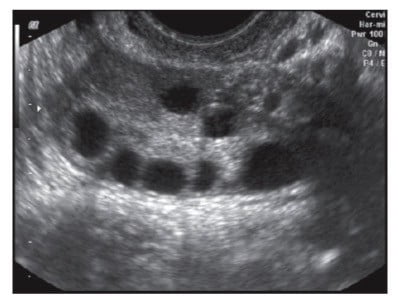

- Antral Follicle Count (AFC): the small number of follicles we count in the ovary. This is something your doctor will likely check at your initial visit and then repeat at your baseline ultrasound.

The way we look at the Antral Follicle Count is through ultrasound. In my office, we use my wand (who I call Wanda). This is also more commonly called a pelvic ultrasound probe. We place this inside the vagina.

I want my patients to be comfortable. You certainly can see the follicles on an abdominal ultrasound. It is just not as easy or exact. But a transvaginal ultrasound is the way to see them quite accurately and that count does translate, for the most part, into the number of follicles (and eggs) that you may be able to grow. However, it does not always correlate with the number of mature eggs you’ll retrieve but knowing your starting number gives you a good idea of what to expect down the line at your next visit.

On cycle day 1 or day 2 you come in. During this baseline ultrasound, I’ll look at your ovaries and count the number of follicles. I’ll review the protocol I’ve decided to use for you. This includes discussing the side effects of the medications you will be taking, things to look out for, when to call me (which is anytime), and then we also do blood work.

Imagine this: I’m taking a small needle and going through the vagina on each side. I call it a vaginal puncture site. There’s no stitching or sutures. There’s nothing like that. However, I’m going through each of those black circles that I showed you on the image of the antral follicle.